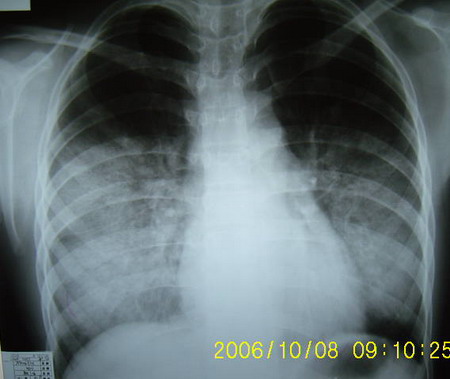

标题: X1082:胸部平片,请会诊

男 18岁 咳嗽 胸痛3天 无咳血 发烧。

主要双肺下叶背段病变,边界不清。

考虑:浸润型肺结核,建议查血象及血沉。

诊断:肺炎

依据:病变跨叶双侧发病,下叶为主,叶间裂增厚,显影,发病时间短,症状不明显可见于年轻患者

双肺中下野片状阴影,密度不均,边界模糊,患者年轻,发病时间短,首先考虑炎症,建议抗炎后复查

双肺部分实变,以渗出为主---大叶性肺炎,治疗复查。

双肺门周围磨玻璃样病变 对称发生 典型的蝶翼征 中央型肺水肿

双肺中下野片状阴影,密度不均,边界模糊,患者年轻,发病时间短,首先考虑大叶性肺炎,建议抗炎后复查请补充相关病史以排除肺水肿结核

考虑肺炎,请结合临床抗炎治疗后短期复查。临床体症不太支持肺水肿。

两肺蝶翼状影:肺水肿.问一下病史,有否农药接触史.

影像与临床表现明显不符[临床表现轻]------支原体肺炎

两中下肺野示大片状密度增高影,边缘模糊。

考虑:1、肺水肿,在问问病史有无其它接触史。

2、支原体肺炎,建议治疗后复查。

两中下肺大片状阴影,边缘模糊,密度较均匀,心脏大小形态无异常,首先考虑两下肺炎,建议结合临床及病史排除肺水肿。

两肺下野大片阴影,边缘模糊,密度尚均匀,考虑大叶性肺炎,建议查wbc和血沉,并抗炎治疗后复查

肺泡蛋白沉着症,依据:肺炎应发热血象升高明显,肺泡蛋白沉着症表现往往与临床不符,表现重临床轻,肺水肿应心脏增大与本病鉴别点

本病人特点1/年龄小病史短2多叶发病心膈角存在肺野中外带病变更著3/无胸腔积液心脏无形态改变4病人无咳血无呼吸困难 因此肺水肿/肺出血病变可除外,暂时先考虑常见的肺炎,先消炎治疗后复查或仔细追问兵史